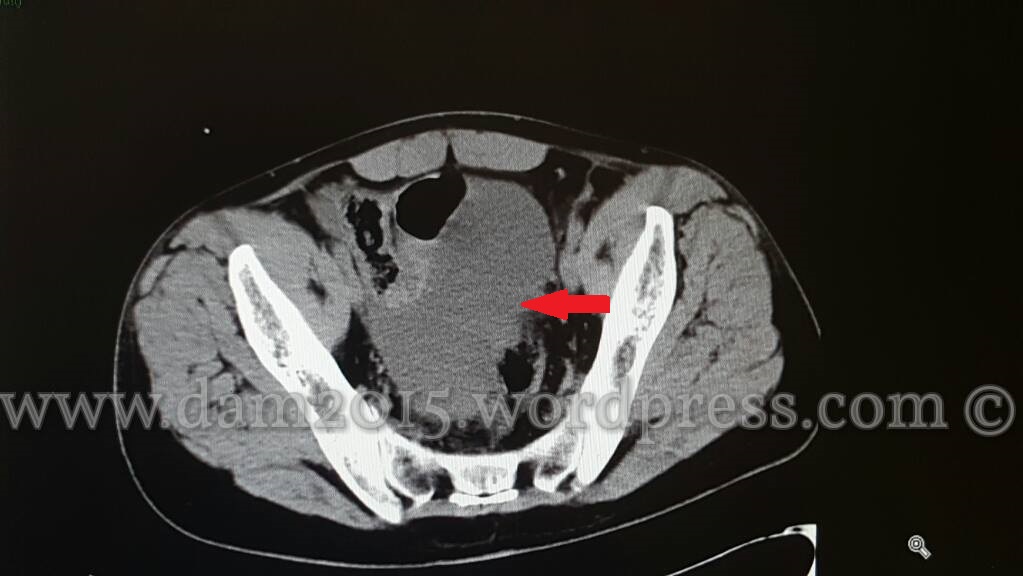

Paziente uomo, 35 anni, con ferita penetrante da arma bianca in fianco sinistro.

Quota fluida di versamento nello scavo pelvico.

Resezione, anastomosi termino-terminale e posizionamento di drenaggi (in numero di 3) di cui uno fatto fuoriuscire dalla soluzione di continuo traumatica in fianco sinistro.

Pinza Klemmer attraverso soluzione di continuo traumatica per posizionare il drenaggio in doccia parietocolica sn.